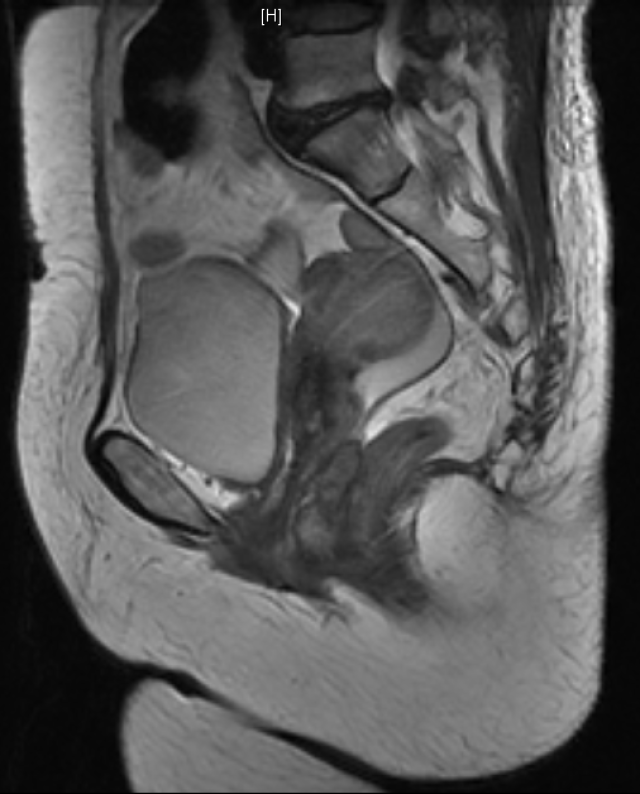

盆腔核磁可见直肠下段前壁增厚,可见不规则肿块形成,位于腹膜反折以下,肠壁较厚处约23mm,阴道后壁受压

阴道后壁与直肠前壁间可见不均质实性肿物,范围约3.8cmx2.9cmx2.3cm,可见较丰富血流信号,近端距阴道口约0.54cm,远端距阴道口约4.22cm